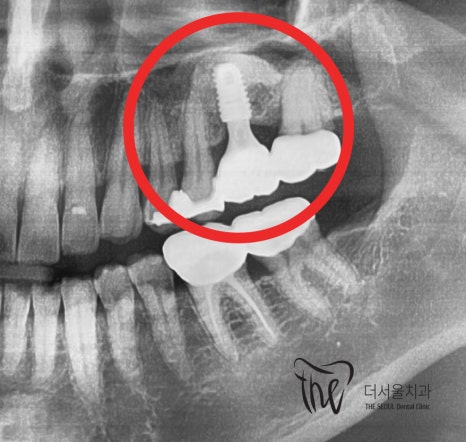

엑스레이에서 보면, 하얗게 보여지는 곳이 있는데

이는 뼈 이식이 잘 되었다는 것을 뜻합니다.

이후, 뼈가 다 아문뒤에 지르코니아 크라운을

연결해드리면서 임플란트 흔들림 문제는 깔끔하게

해결이 되었습니다.

이렇게, 대략 6개월 가량이 소요되면서